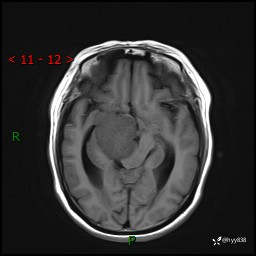

颅脑MRI平扫+增强